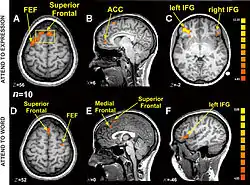

Research using functional magnetic resonance imaging of the brain suggests that cognitive and affective-expressive forms of communication and self-reflection have distinct neural bases.[50] Clinical findings have long suggested that verbalizations are often very incoherent when the individual is trying to put into words something deeply emotional.[51] Identification of words naming emotions (happy, neutral, sad) was found to be faster than identification of corresponding facial expressions. Recognition of face expressions was more difficult to suppress in favor of the recognition of words than vice versa, the two conditions presenting different patterns of brain activation. These experimental results suggest that reading and recognition of face expressions are stimulus-dependent and perhaps hierarchical behaviors, hence recruiting distinct regions of the medial prefrontal cortex.[48]

- Ovaysikia S, Tahir KA, Chan JL, DeSouza JF (January 2011). "Word wins over face: emotional Stroop effect activates the frontal cortical network". Front. Hum. Neurosci. 4: 234. doi:10.3389/fnhum.2010.00234. PMC 3020489. PMID 21258644.